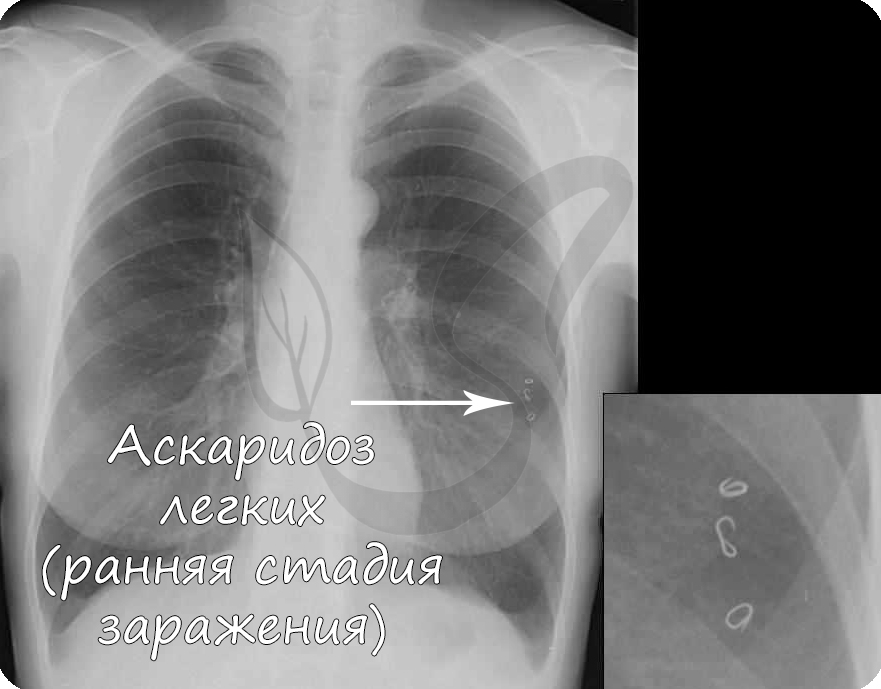

➡ Дальше новорожденные личинки с помощью острого конца хвоста проникают в кровеносную систему, где с потоком крови движутся по направлению через сердце к лёгким. Для развития особи нужен кислород, который в достаточном количестве есть в лёгких. Они на некоторое время остаются в альвеолах легких. Если в это время сделать рентген, можно увидеть скопления личинок. Симптомы в это время напоминают воспаление лёгких.

2. Рентген грудной клетки и живота для обнаружения взрослых особей аскариды человеческой

По отдельности анализы имеют не столь успешный результат. Проводить их нужно в комплексе, чтобы точно диагностировать аскаридоз. Рентгенограммы должны делаться два-три раза с промежутком в три дня. Несколько раз делаются и анализы крови и кала. После выявления изменений в организме делается вывод о наличии заражения.